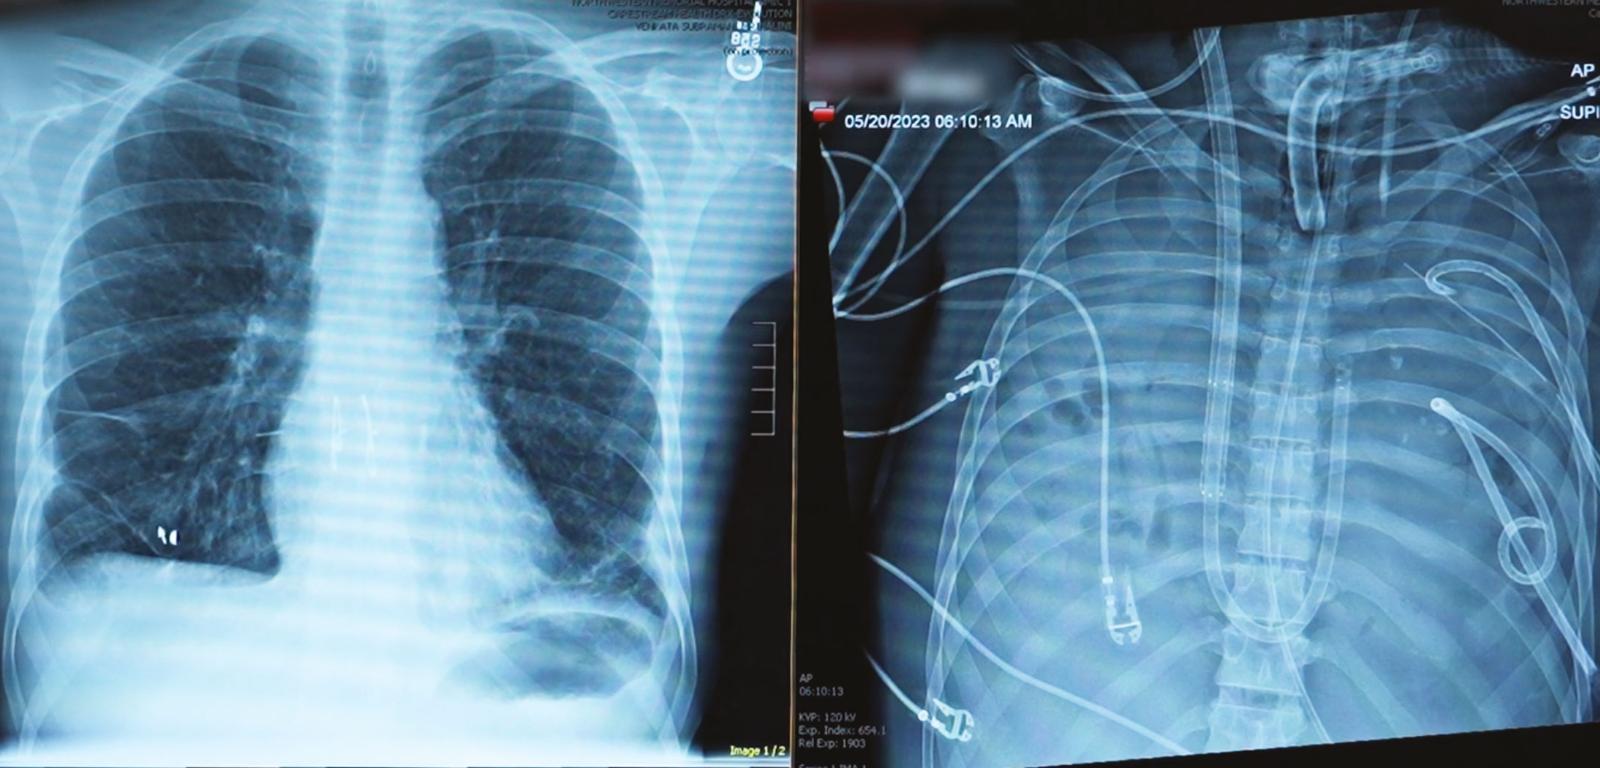

Zdjęcia rentgenowskie pokazują klatkę piersiową pacjenta – najpierw z płucami, a następnie po ich usunięciu. Sztuczny system podtrzymywał chorego przy życiu przez dwa dni – całkowicie bez płuc. Zdjęcia rentgenowskie pokazują klatkę piersiową pacjenta – najpierw z płucami, a następnie po ich usunięciu. Sztuczny system podtrzymywał chorego przy życiu przez dwa dni – całkowicie bez płuc. Northwestern Medicine

W 2023 roku chirurg klatki piersiowej Ankit Bharat z Northwestern Memorial Hospital został wezwany do umierającego 33-letniego pacjenta. Bharat wspomina, że u mężczyzny rozwinęło się wtórne zakażenie jednym z „najgroźniejszych szpitalnych drobnoustrojów” – bakterią Pseudomonas aeruginosa – i że został on podłączony do respiratora. Płuca pacjenta wypełniały się płynem i ropą, nerki przestawały działać, a serce biło szczątkowo, mówi Bharat. „On faktycznie umierał”.